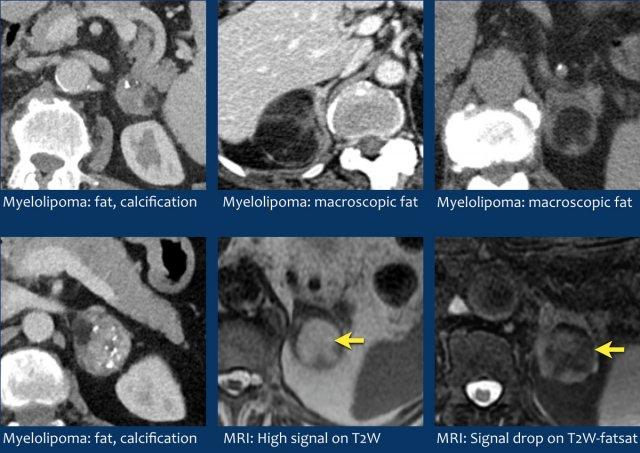

U tủy mỡ (Myelolipoma)

U tủy mỡ là các khối u lành tính cấu thành từ các thành phần tủy xương.

Thông thường chúng dễ nhận biết trên CT hoặc MRI vì chứa các vùng mỡ đại thể.

Vôi hóa gặp trong 24% các trường hợp.

Khối tuyến thượng thận thấy trên CT ở đây chứa mỡ đại thể, đặc hiệu cho chẩn đoán u tủy mỡ.

Hình ảnh CT của một khối tuyến thượng thận khác chủ yếu cấu thành từ mỡ đại thể.

Chẩn đoán: u tủy mỡ.

Trong 10% trường hợp, u tủy thượng thận có vôi hóa và thường có nhiều nang (mũi tên vàng).

Dấu hiệu kinh điển được gọi là “dấu bóng đèn” (light bulb sign), biểu hiện bằng tín hiệu cao đồng nhất trên chuỗi xung T2W, được ghi nhận trong 65% trường hợp [4].

Sự hiện diện của mỡ đại thể giúp nhận diện dễ dàng trên CT hoặc MRI.

Tỷ trọng trên CT không tiêm thuốc sẽ thấp hơn 0 HU rõ rệt.

Trên MRI, các phần mỡ sẽ tăng tín hiệu trên chuỗi xung T1W không bão hòa mỡ và mất tín hiệu trên chuỗi xung T1 hoặc T2W có bão hòa mỡ.

Vôi hóa được ghi nhận trong khoảng 24% trường hợp.